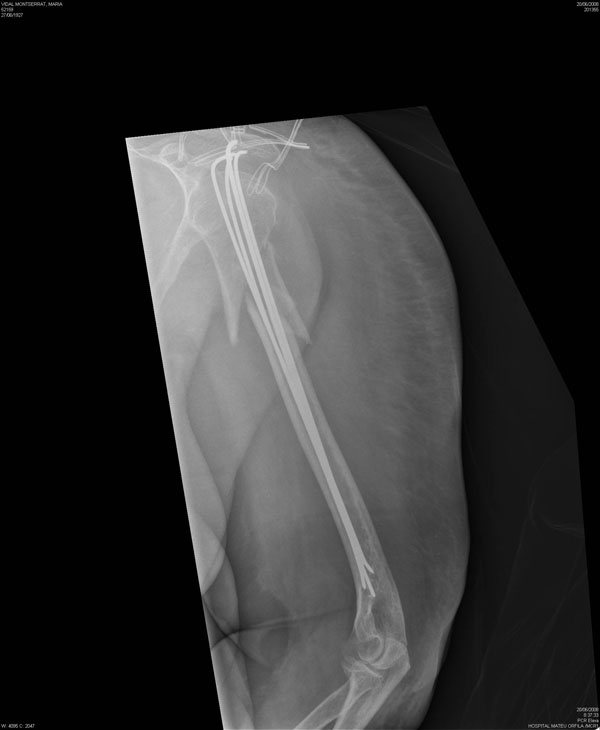

Fractura de húmero tras osteosíntesis con clavo gamma.